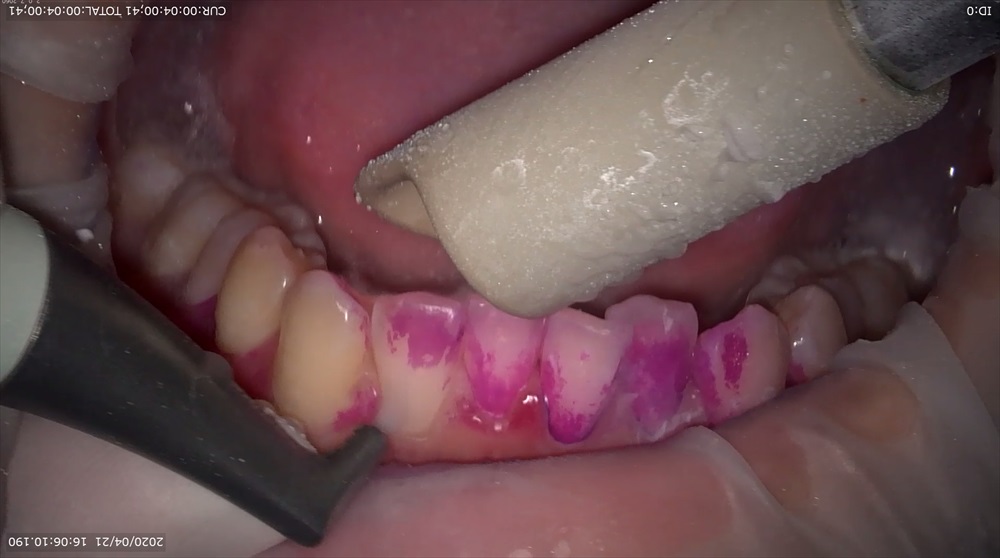

どうやって抑制していくかというと、当医院ではエアフローパウダーを使用していきます。

アミノ酸のグリシンというパウダーを使用し、歯面を傷つける事なく歯の面や歯周ポケット内にまで行き渡り除去していきます。

患者さんからはスッキリした、痛みもなく気持ちいいと言う声をいただいています!!

又、当医院ではマイクロスコープ(手術用顕微鏡)をメンテナンスでも使用し患者さんの実際に歯垢が付いているところやパウダーを使用して落としている映像をみていただいています。